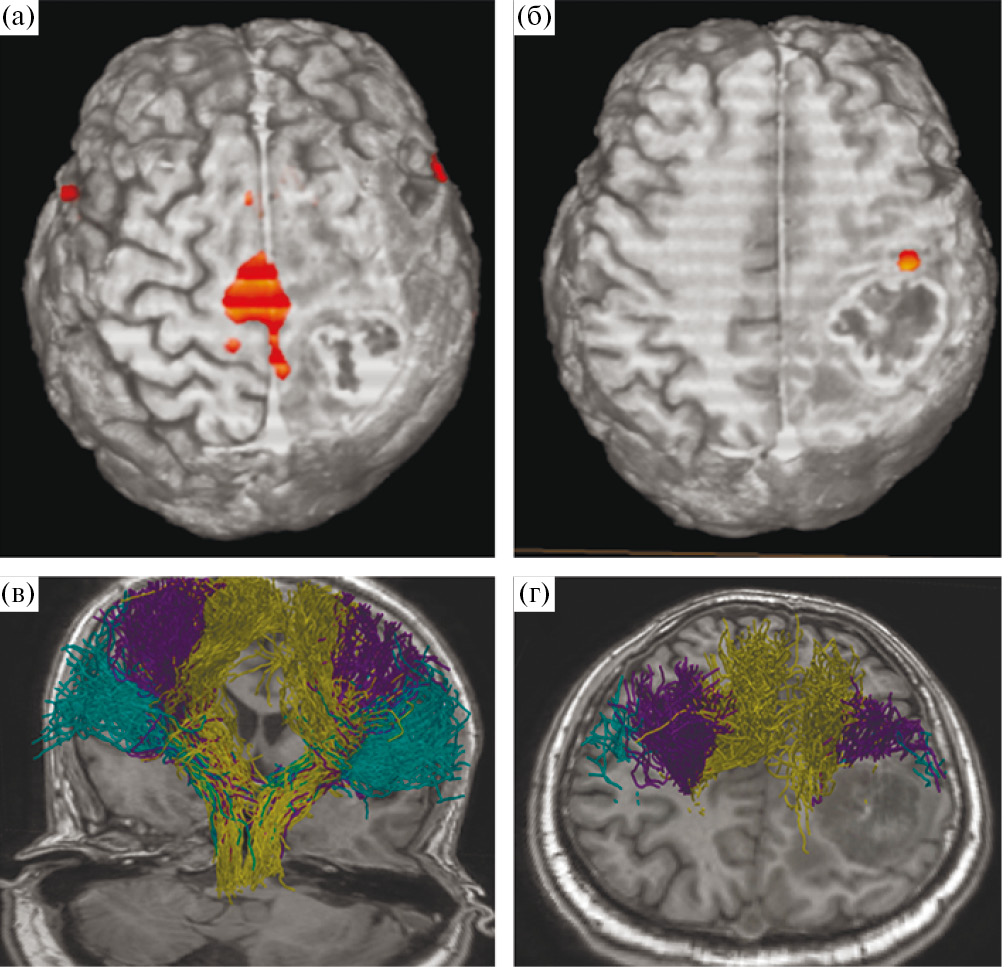

Аласенс (препарат 5-аминолевуленовой кислоты) вводился перорально за 2 ч до разреза ТМО из расчета 20 мг/кг. Из исследования были исключены 12 пациентов, у которых не отмечалось визуальной флуоресценции во время операции. Всем пациентам была проведена оценка мышечной силы до операции, на первые и седьмые сутки после хирургического лечения, выполнена предоперационная МРТ (Т1, Т2, Т2-FLAIR, DWI, T1+C, DTI) с определением расстояния от опухоли до КСТ и типа взаимоотношения между трактом и новообразованием. Было показано, что из 108 пациентов у 21 (19.4%) наблюдался интактный КСТ, у 43 (39.8%) – смещенный, у 34 (31.5%) – смещенный и инфильтрированный, у 8 (7.4%) – инфильтрированный, и только в одном наблюдении опухоль располагалась в структуре тракта, расщепляя его (рис. 1).

Рис. 1. (а) – пример интактного КСТ по данным ДТ-трактографии у пациента с глиобластомой. Тракты симметрично расположены и не отличаются значимо по объему. (б) – пример смещенного КСТ, по данным ДТ-трактографии у пациента с глиобластомой. Тракты не вовлечены в опухоль, однако положение их отличается. (в) – пример инфильрированного КСТ, по данным ДТ-трактографии у пациента с глиомой Grade IV. Несмотря на вовлечение КСТ в опухоль, по данным Т2-FLAIR отмечается правильное, симметричное положение тракта. (г) – пример смещенного и инфильтрированного КСТ, по данным ДТ-трактографии у пациента с глиобластомой. Тракты расположены асимметрично и вовлечены в зону отека-инфильтрации. (д) – пример расщепленного тракта у пациента с анапластической астроцитомой. Опухоль располагается внутри КСТ, расщепляя его волокна.

Fig. 1. Different types of relationship between the corticospinal tract and the tumor according to MR-tractography (intact, displaced, infiltrated, displaced and infiltrated, split).